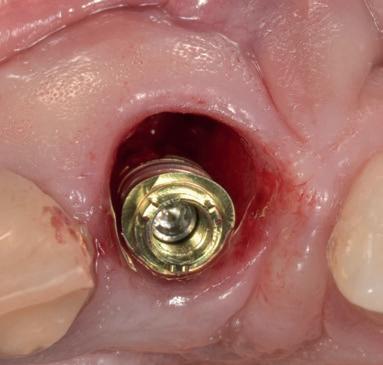

De implantaatplaatsing en de beslissende fout (afbeelding 1-13)

De extractie verliep voorspoedig, waarbij ik zoals al-

primaire stabiliteit van 60 Ncm.

11. Röntgenfoto ter controle van de plaatsing en de angulaire. Dit bone-level implantaat werd 4 mm onder de weke delen geplaatst.

12. Direct post-op. Een direct geplaatste tijdelijke kroon. Vastgezet met een torque van 20 Ncm en gehecht met prolene 5/0.

tijd probeerde de buccale botlamel intact te houden. Dit is cruciaal voor latere botbehoud en implantaatplaatsing. Na curettage en spoelen van de alveole beoordeelde ik de situatie opnieuw: de botcondities leken gunstig voor een immediaat implantaat.

Hier begon echter de cruciale fout in mijn klinisch besluitvormingsproces. In mijn streven naar maximale primaire stabiliteit - wetende dat immediaat belasten enkel mogelijk is bij hoge stabiliteit -on-

13. Röntgenfoto ter controle van de pasvorm van de direct geplaatste tijdelijke kroon.

derprepareerde ik de osteotomie. Dit betekende dat ik een iets te smal implantaatbed creëerde, in de hoop dat het implantaat stevig in het bot verankerd zou worden.

Op papier leek dit een logische stap: het MegaGen AnyRidge-implantaat dat ik koos, gaf me een stabiliteit van 60Ncm—een cijfer dat vertrouwen gaf in immediaat belasten. Maar in mijn enthousiasme had ik onvoldoende rekening gehouden met de biologische gevolgen van overmatige compressie.